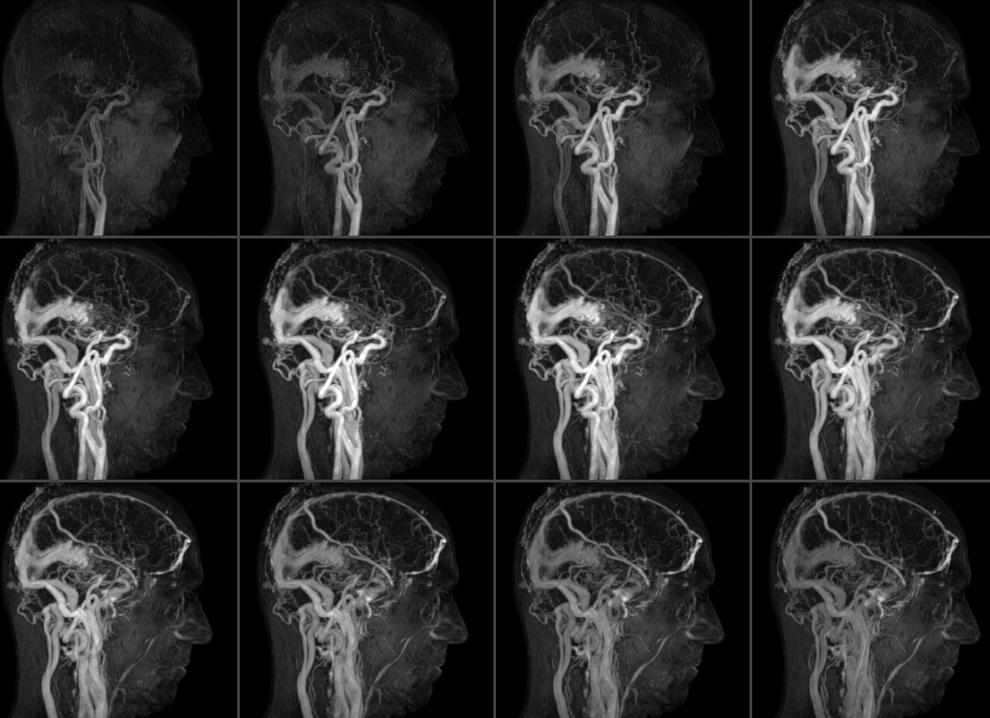

Ангиограмма сосудов головного мозга

C помощью церебральной ангиографии выполняется рентгенологическое исследование мозгового кровообращения в разных фазах: артериальной, капиллярной и венозной.

Рентген-съемки головы производят в переднезадней и боковой проекциях. Проявленные снимки представляют собой ангиограмму, оценивающую состояние церебральных сосудов. При необходимости вводят контраст дополнительно и делают новую серию снимков. Исследование оттока венозной крови выполняют с помощью серии снимков после прохождения контраста по тканям. Длительность процедуры – около часа.